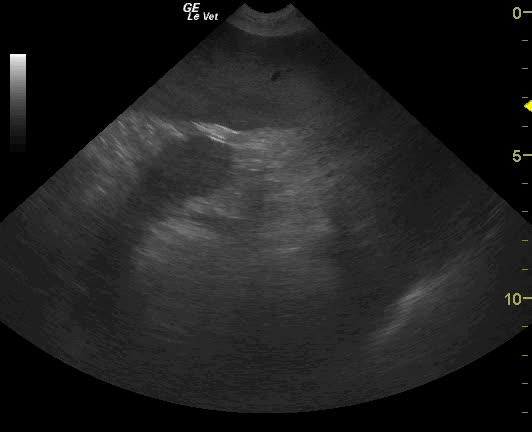

Severe gastric air artifact is noted when imaging the stomach. The normal pylorus is not visible from the right 11-13 intercostal approach suggestive for pyloric displacement. Splenic congestion and splenomegaly is present.